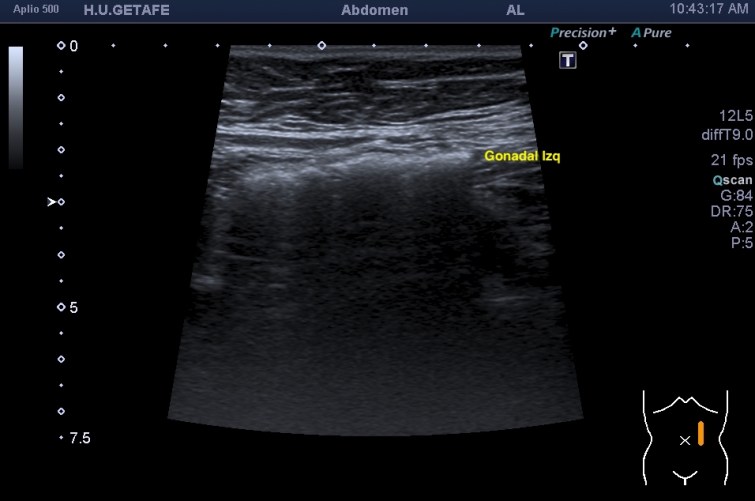

Lo que ves en estas imágenes que te voy a poner aquí son los hallazgos ecográficosque he podido visualizar hoy. Los voy a complementar con la correlación con las imágenes de TAC. En este caso específico con la eco solo se pudo corroborar los hallazgos del escáner, que a nivel anatómico arroja un mejor desarrollo de la anatomía regional implicada en el proceso.

6En el corte longitudinal de la imagen 1 ya se ve una vaso perimetrado por una imagen hiperecogénica, no compresible a la presión con la sonda convexa. En la imagen 2 con la sonda lineal se observa el enrejado habitual de los stents, que en otras ocasiones ya hemos comentado en otro post en localización distinta.

Finalmente, imagen 5 y 6 que te enseñan el tratamiento aplicado a las gonadales de forma bilateral, embolizadas con material hiperecogénico en su interior que en la reconstrucción coronal del CT se objetiva como una imagen bilateral brillante lateral a los grandes vasos.